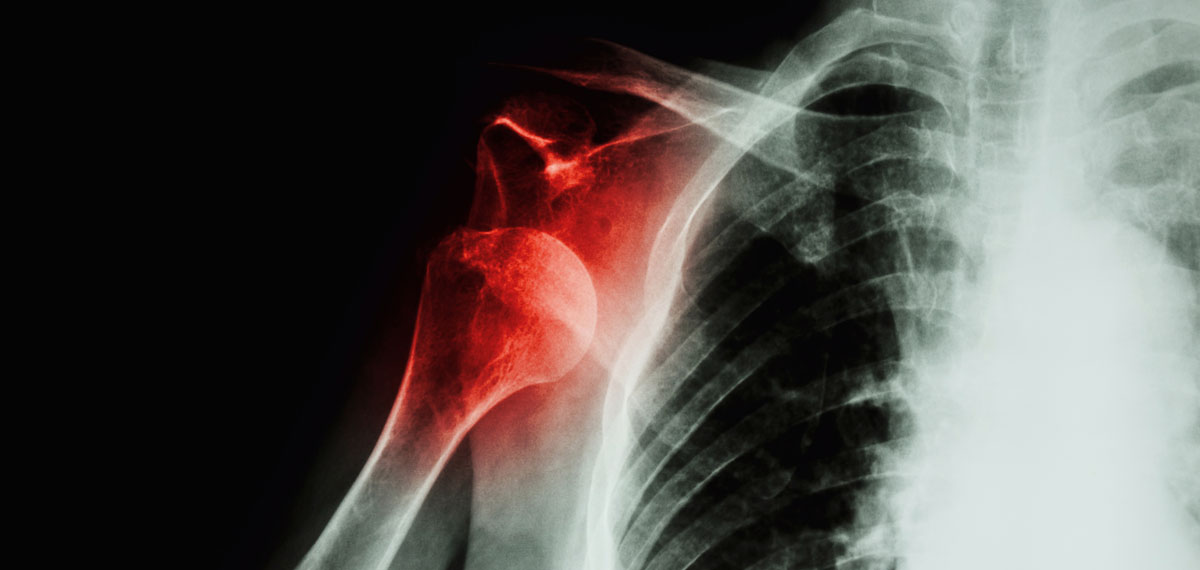

What Is An Unstable Shoulder . Shoulder instability develops in two different ways: Shoulder instability happens when the ball of the shoulder isn't restrained properly by ligaments or cartilage. It can occur as dislocation,. Shoulder instability refers to shoulder joints that have a high risk of slipping out of place. One of the most common causes of shoulder instability is dislocation after sustaining trauma to the area such as a direct blow to the shoulder or a sudden jerk of. Shoulder instability is an issue affecting the structures surrounding the shoulder joint, typically when these structures do not. Severe injury, or trauma, is often the cause of an initial shoulder dislocation. There are three common ways that a shoulder can become unstable: Due to a specific injury or. Shoulder instability can occur following a traumatic accident such as a fall or collision with another athlete or object.